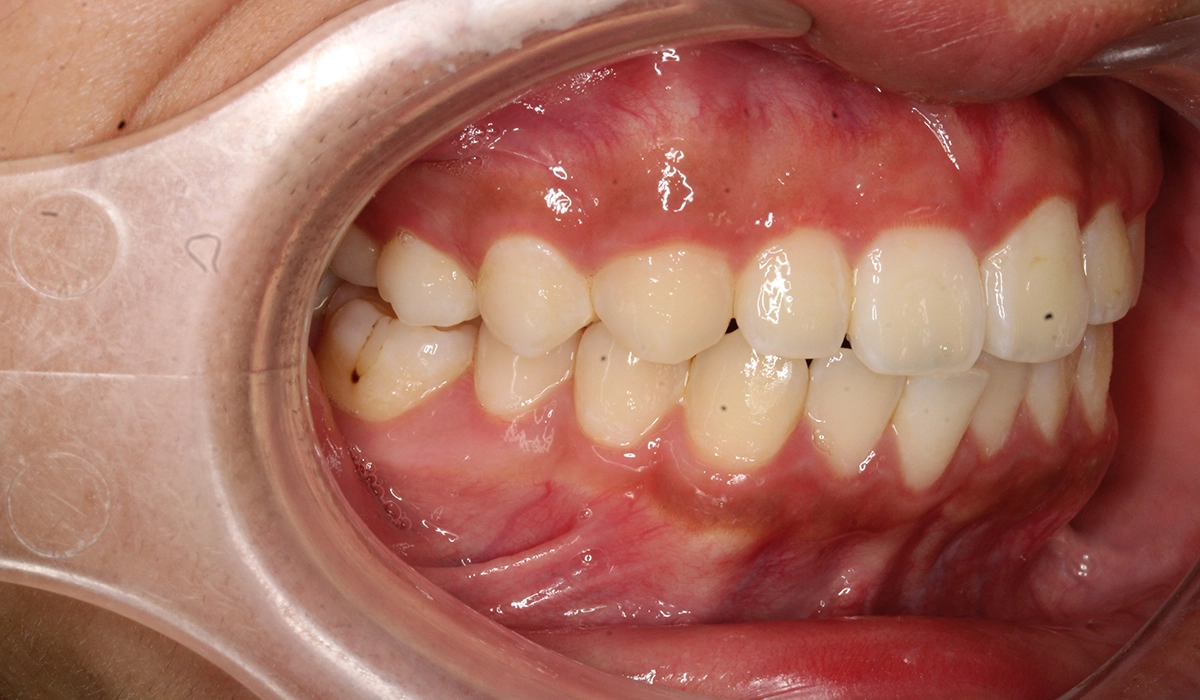

術前:左側